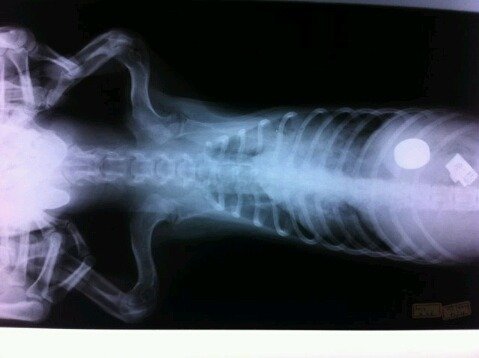

폐렴으로 인하여 엑스레이를 찍었습니다.

그때

이상한 물체들이 발견되었습니다...

호흡이 약하고 뱃속에 이런 쇠덩어리들이 있어서 살수없을거라고..

진단을 했었는데요..

4개월령 비글 아가 뱃속에서 나온..

100원짜리 3개 300원과.

뭔지 알수없는 이상한 얇고 까칠한 쇠.